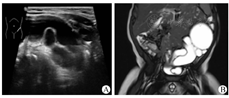

本研究患儿的纳入标准:①术前B型超声和磁共振尿路成像(magnetic resonance urography,MRU)检查明确诊断为单侧POM(图1);②排尿期膀胱尿道造影(voiding cystourethrography,VCUG)检查排除膀胱输尿管反流及后尿道瓣膜引起的输尿管扩张,并进行放射性核素肾静态扫描(dimercaptosuccinic acid scan,DMSA)检查肾功能及肾瘢痕。本研究所有患儿均为0~36个月的婴幼儿,并符合以下手术指征(≥1项):①出现临床症状或者反复发作的尿路感染;②超声检查提示输尿管进行性扩张;③放射性核素肾脏显像检查提示分肾功能<40%或连续分肾功能检查提示相差≥5%[7]。所有手术均由患儿监护人自行选择采用RALUR或LUR。本研究已通过我院伦理委员会审查(2021-IRB-125),并获得所有参与研究患儿家属的知情同意。